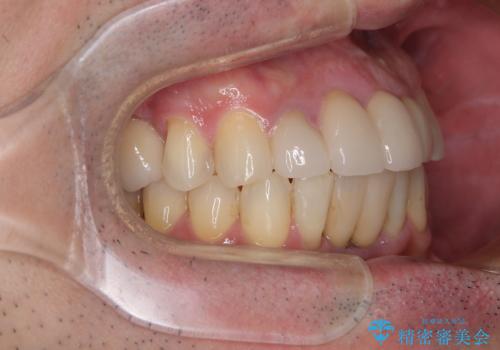

矯正治療を行いながら、欠損部はインプラントによる補綴治療を希望されたため、補助装置を用いたワイヤー矯正によりスペースを確保しながら歯列を整え、適宜インプラントを埋入していくこととしました。

上顎前歯もインプラントを希望していらっしゃいましたが、両隣の歯根が近接しており、インプラントは困難と判断したためオールセラミックブリッジによる補綴治療を前提として治療を開始することとしました。

下顎前歯にインプラントを2本埋入するのは非常に困難であり、どうしても歯肉位置に土台の金属色が見えてしまう仕上がりとなりました。無理をせずに1本のみの埋入とするか、ブリッジを提案しましたが、患者様の強い希望により、2本埋入することとなり、大変満足していただけました。